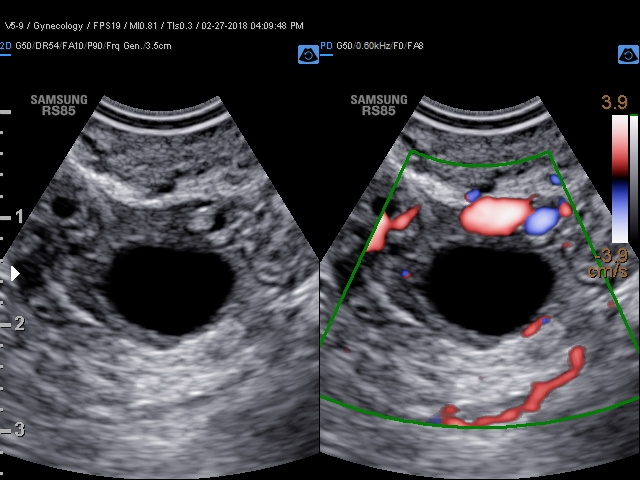

Trojrozměrná vizualizace průtoku krve

LumiFlow ™ je funkce, která vizualizuje průtok krve trojrozměrně, tak aby usnadnila intuitivně pochopit strukturu průtoku krve a malých cév.